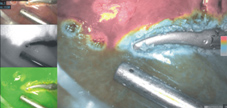

則是直接將ICG 注射到要切除肝段的門靜脈分枝中,讓要切除的範圍會亮起來,所以外科醫師切肝時,只要循著亮與不亮的界線,便可以精準地切除。利用這種原則來執行肝癌手術,不僅可以將可能的微小病灶一併切除,更因?能避開膽管、血管分枝而大幅降低術後併發症,縮短住院時間。

然而要精準地將想要的門靜脈分枝染上ICG非常困難。傳統上是在術中超音波定位下,進行門靜脈穿刺,但往往血管分枝太細而不易成功。而且如果沒有術前影像立體重組 (如圖二) ,外科醫師也很難確定該染哪一枝門靜脈分枝?因此要使用ICG正染法螢光導引進行微創精準肝切除,即使是最熟練的團隊也大概只有一半的成功率。本院微創肝臟手術團隊和影像醫學部黃俊傑醫師整合院內資源,利用院內多功能的整合式開刀房(Hybrid OR),不僅可以用血管攝影的技巧,精準標定需要切除的肝段,更首創術中電腦斷層確認切除範圍。確保足夠之切除邊界。李先生的3D立體微創肝癌切除更是以這種技術完成,真正體現了科技提昇人眼和人腦的極限,開啟了外科手術的新境界。

圖三、腹腔鏡螢光導引精準肝癌切除

圖四、高度選擇性門脈ICG螢光顯影